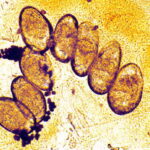

Histologic examination of a specimen containing a burrow reveals that the burrow in almost its entire length is located within the horny layer . Only the extreme, blind end of the burrow, where the female mite is situated, extends into the stratum malpighii . The mite has a rounded body and measures about 350 to 450 IJm in length and 250 to 350 IJm in width . |

In the papulovesicular form of scabies, spongiosis is present in the stratum malpighii near the mite to such an extent that formation of a vesicle is often the result. Even if no mite is found in the sections, the presence of eggs containing larvae, of egg shells, or of fecal deposits (scyballa) within the stratum corneum is indicative of scabies . The dermal infiltrate in sections containing mites shows varying numbers of eosinophils. |